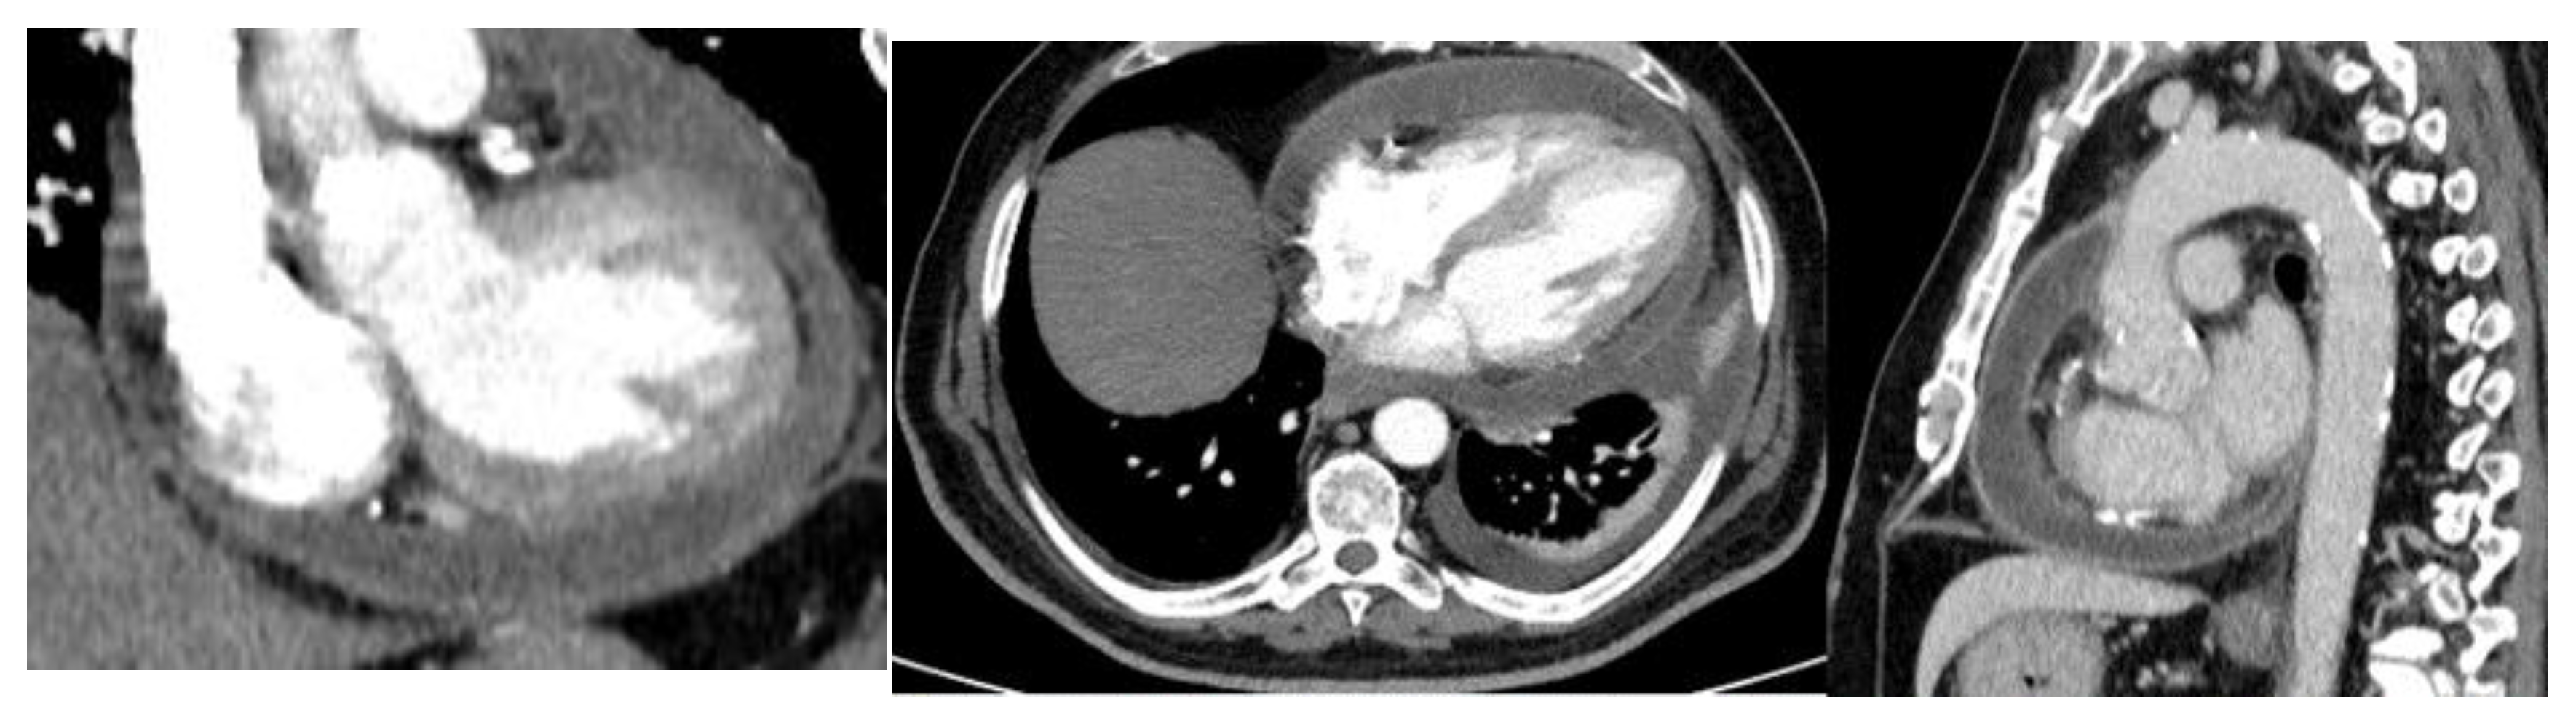

A pericardiotomy via median sternotomy approach was performed, revealing 800 mL of sero-hematic fluid. The epicardial surface showed a shaggy fibrinous exudate, a rare manifestation of fibrinous pericarditis (Figure 3). Decortication started from the left ventricle to the right ventricle to avoid pulmonary edema; after freeing the mid-anterior part, the dissection was extended laterally to both the right and left side using sharp and blunt techniques, carefully finding a dissection plane between the epicardium and the pericardium. The dissection was completed by resectioning a particularly tough adherence involving the cardiac apex. A phrenio-phrenic pericardiectomy was not considered necessary; furthermore, it could even be dangerous. The left pleura was opened, and the effusive pleural liquid was drained. Cultures of pericardial and pleural fluid were sent to be analyzed. The pericardial and pleural fluid was positive for S. agalactiae. The anatomo-pathologic exam confirmed the diagnosis of fibrinous pericarditis, showing fibrinous-granulomatous tissue associated with the presence of leukocyte exudate and blood clots.

Figure 3. Effusive-constrictive pericarditis. Intraoperative image shows residual pericarditis after pericardiectomy.